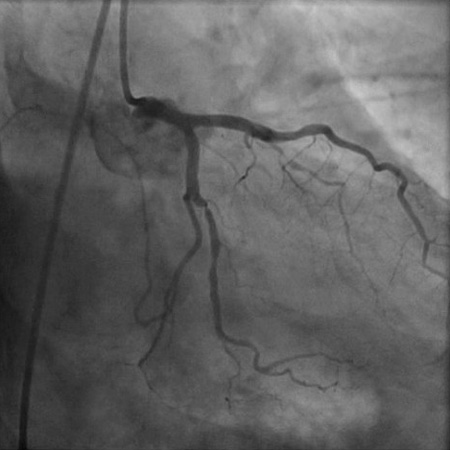

Angiograma (projeção caudal oblíqua anterior direita) em homem de 55 anos com história de 1 mês de angina ao esforço físico. Há uma estenose proximal de 90% da marginal obtusa 1, o que explica a isquemia lateral do paciente

Do acervo do Dr. S.D. Fihn; usado com permissão